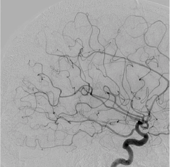

いわゆるカテーテル治療のことを言います。細いカテーテルを、AVMを栄養している動脈へ誘導して、「塞栓物質」と呼ばれるものを使用して、AVMへの血流を遮断する方法です。「塞栓物質」は、nBCAと呼ばれる医療用の接着剤や、Onyxと呼ばれるポリマーが多く使用されます。 脳を直接触る手術ではないため、患者さんへの負担は少ない治療ですが、この治療のみでAVMを完治させることは困難です。このため、外科的摘出術や放射線外科治療の前段階の治療として、サイズを縮小させたり、血流を減少させることを目的に行われることが多い方法です。

CTやMRIに加えて、脳血管撮影を施行した上で、治療方針を決定しています。出血を起こしていないものに関しては、敢えて治療をせずに、経過観察を行う場合もあります。安全に摘出可能と判断できる病変に関しては、血管内治療による塞栓術を併用して、外科的摘出術を行います。摘出術が困難ですが、治療が必要と判断される病変に関しては、塞栓術を行った後に、放射線治療を行うことをお勧めしています。 当施設には、ガンマナイフやサイバーナイフが設置されておりませんが、関連施設にご依頼させて頂き、治療前後のフォローを綿密に行っております。